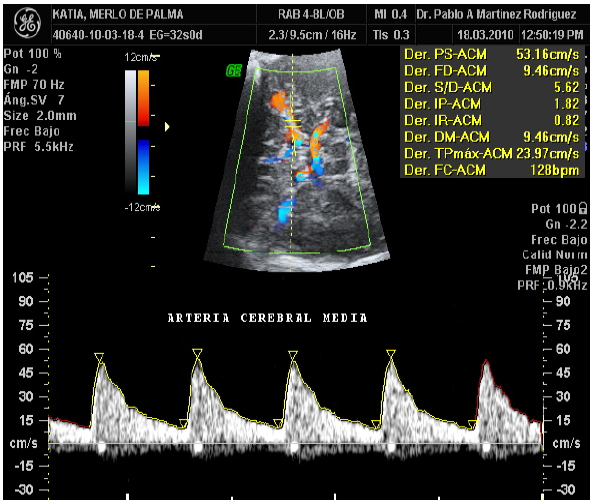

A las pacientes se les realizó la flujometría Doppler de las arterias umbilical y cerebral media, con un equipo de ultrasonografía Marca Toshiba Nemio, con un transductor convex volumétrico 3,5 Mhz. La obtención del flujo de la arteria umbilical se realizó a nivel de asa libre del cordón umbilical o en la inserción placentaria, en ausencia de movimientos respiratorios fetales, ya que estos pueden alterar la onda y simular ausencia de flujo diastólico. Se debe identificar el vaso y utilizar escalas de velocidad medias (entre 20 y 40 cm/s) para la identificación selectiva del vaso. El ángulo de insonación debe ser siempre inferior a 30º, lo cual es fácil en este vaso. Aunque los índices Doppler son matemáticamente independientes de este ángulo, si es excesivo afecta la precisión de la medida. El tamaño de la muestra debe ser equivalente al diámetro de la arteria y debe colocarse en el centro del vaso. Se utilizó el asa libre por facilidad técnica, ya que la mayoría de curvas de referencia se han realizado a este nivel y todos los estudios randomizados que han establecido su utilidad han usado esta porción (1,23,24).

En cuanto a la evaluación de la arteria cerebral media esta se identifica en un corte axial craneal a nivel del Polígono de Willis, observándose su trayecto de unos 2 a 4 cm, desde su parte proximal en la salida en la carótida interna hasta su parte distal adyacente al hueso parietal. Esta discurre a través del ala mayor del esfenoides. Existen diferencias a tener en cuenta entre los diferentes segmentos de la ACM en cuanto a la medición, cuanto más distal al polígono, mayor es la pulsatilidad; por otro lado, en sus porciones más distales se divide en 2 a 4 vasos por lo que su evaluación es menos representativa. Debido a ello el estándar es evaluar el vaso en su porción proximal cerca de la salida de la carótida interna (23,24,1).

Para realizar la medición, se debe identificar el vaso con Doppler color y utilizar escalas de velocidad media mayores de 50 cm/s, para la identificación selectiva del vaso debe hacerse con un ángulo de insonación de 0°, se realiza la exploración en ausencia de movimientos respiratorios fetales, tomando en cuenta no ejercer una presión excesiva sobre la calota fetal, pues esta presión ejercida puede aumentar la pulsatilidad y disminuir las velocidades máximas. Este fenómeno es más notable a edades gestacionales precoces por ser la calota más deformable. Deben obtenerse tres o más OVF de similares características para la medición, ampliando la pantalla en tres cuartas partes con el fin de realizar la medida adecuada (23,24,1).

Para referir criterio de normalidad del IP, cuando este se encuentra entre el P10 y el P95, por lo que ante una vasodilatación el IP ACM, puede encontrarse <P5 de manera persistente en dos mediciones separadas > 12 horas. Si existe redistribución el índice cerebro-placentario (IPACM/ IPAU) su valor estará <P5 y un aumento de las velocidades sistólicas >1,5 MoM de manera constante.